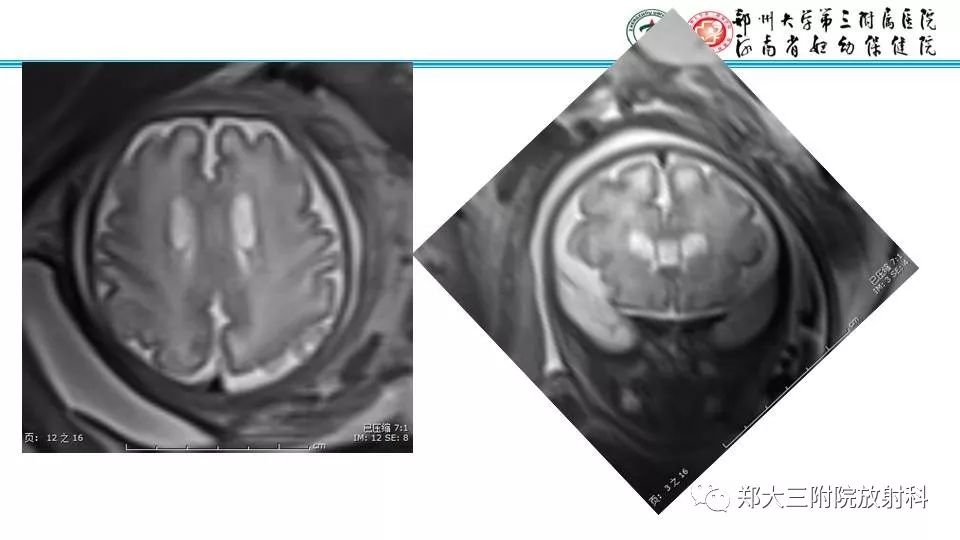

【PPT】室周假性囊肿-4